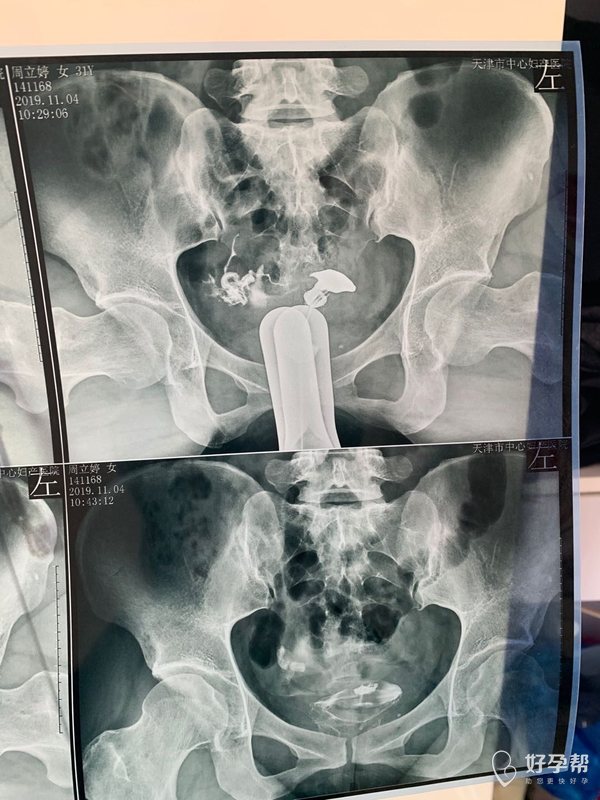

我今年34岁,右侧输卵管粘连,左侧宫外孕输卵

这种必须做手术么还是取了胚胎不是非要做

这个手术不是非得要马上做,需要根据你的年龄、生育计划等来综合评估并权衡利弊后再决定是否需要手术以及什么时候做。如果是做试管通常为了避免输卵管积液及炎症因子逆流至宫腔影响胚胎着床等,会行输卵管结扎等手术,这个手术通常在移植前完成